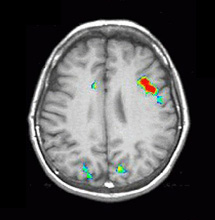

| Images | ![]() | ||||||

| Activation | Left hemisphere activation is clearly greater. The activation is in the following areas: Broca's (image 5), Wernike's (images 4 and 5), left supramarginal gyrus (heteromodal associative area, in image 5), left motor and premotor strip. The primary auditory areas are also activated predominantly on the left. |